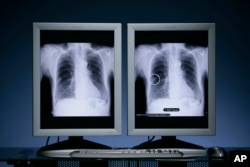

Công nghệ OnGuard Chest X-ray CAD (computer-aided detection) của công ty Riverain phát hiện các cục u bướu hạch nhỏ đáng nghi có thể là dấu hiệu của ung thư phổi giai đoạn sớm giúp cải thiện tỷ lệ sống sót cho các bệnh nhân. (PRNewsFoto/Cleveland Clinic and Riverain Medical)